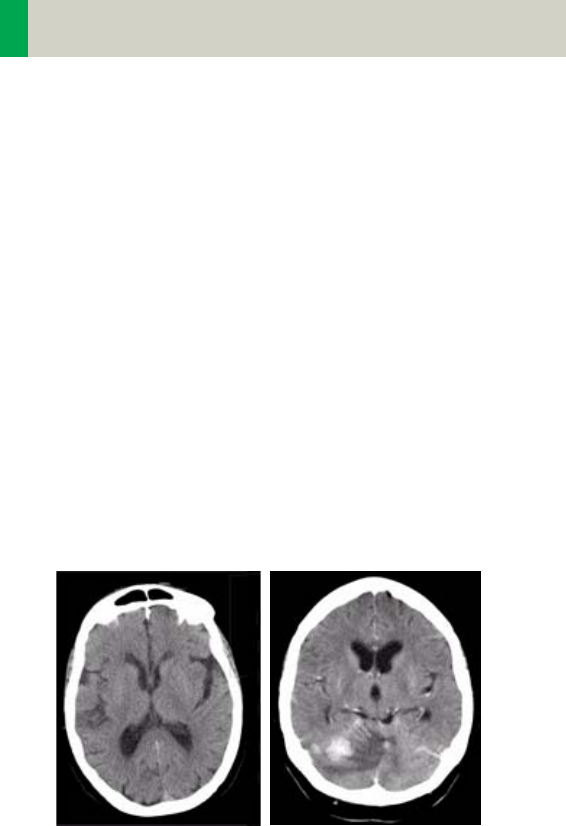

Automatic Bone Correction

The head protocols provide significant improvements

regarding image quality for heads. An automatic bone

correction algorithm has been included in the standard

image reconstruction. Using a new iterative technique,

typical artifacts arising from the beam-hardening

effect, for example, Hounsfield bar, are minimized

without additional post-processing. This advanced

algorithm produces excellent images of the posterior

fossa, but also improves head image quality in general.

Bone correction is activated automatically for body

region “Head”. The reconstruction algorithm for “Head”

also employs special adaptive convolution kernels

which help to improve the sharpness-to-noise ratio.

More precisely, anatomic contours are clearly dis-

played while noise is suppressed at the same time

without causing a blurring of edges.

Head image without

correction.

Head image with

corrections.